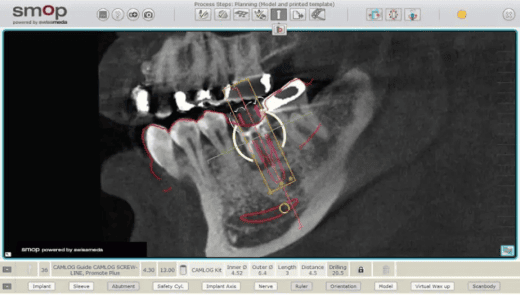

治療計画の作成と設計

患者さま一人ひとりに合わせて、最適な治療計画をご提案します。

顎の骨に人工歯根を埋め込みます。事前にシミュレーションを行い、その通りに治療を進めるためのガイドを作成しますので、ご安心ください。